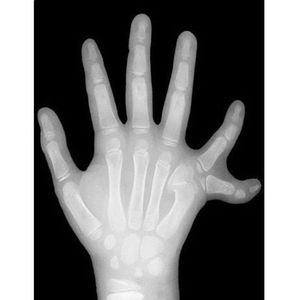

Here's an X-ray (front view) of the hand of a young child showing six fingers (polydactyly). Swipe it up to see a left foot with the same condition. Polydactylism is a fairly common congenital abnormality. Chances are you'll see this at least once or twice, it's that common! The extra digit is usually a small piece of soft tissue that can be removed. It can contain bone without joints and rarely even be a complete functioning digit but people choose to remove it surgically due to social reasons.